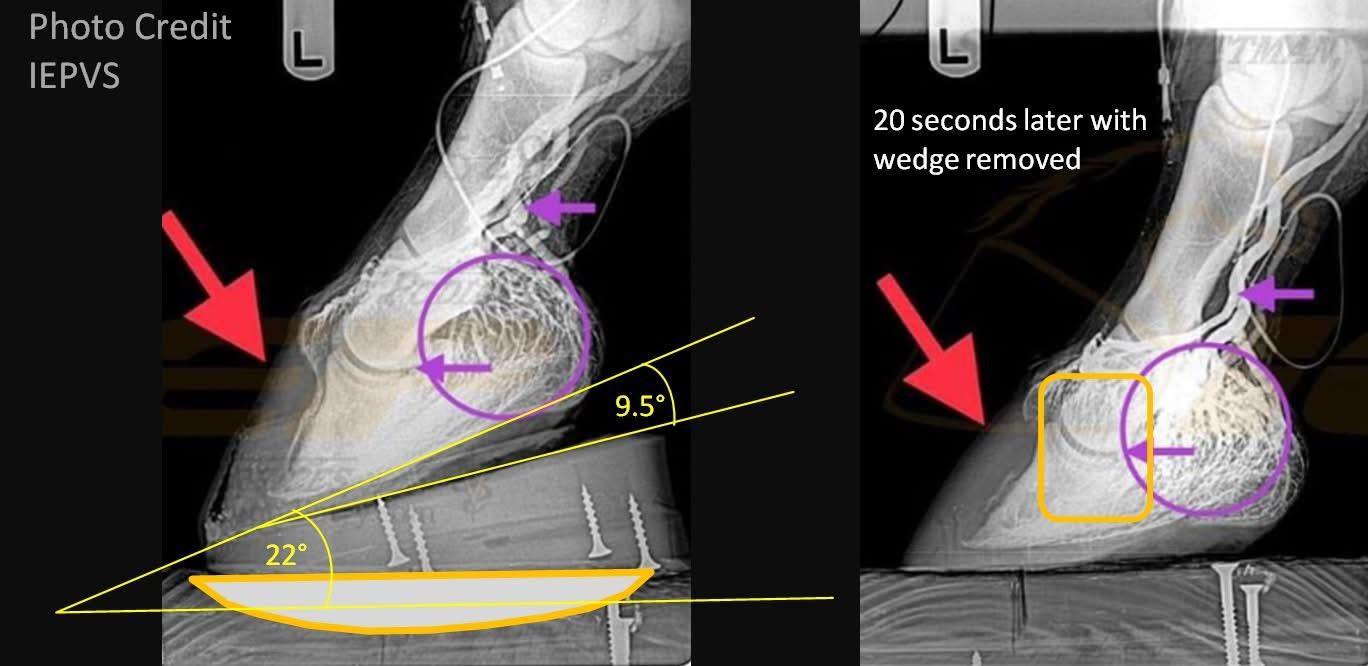

Biomechanical Rationale for Plantar Heel Extensions in the Management of Chronic Hindlimb Proximal Suspensory Desmopathy Caldwell M and Madden N. Scientific Horseshoeing Limited. 116, Newcastle Road, Talke, Staffordshire. ST71SA. Email info@hoofflix.com Introduction Chronic proximal suspensory ligam...

Chronic Proximal Suspensory Ligament Desmopathy in Horses: Biomechanics, Postural Adaptation, Hoof Capsule Morphology, and Treatment Strategies Caldwell M. N. Scientific Horseshoeing, 116, Newcastle Road, Talke, Staffordshire. ST7 1SA. Email info@hoofflix.com 1. Introduction Chronic desmopathy of th...

Dr. Mark Caldwell PhD; FWCF. HoofFlix. CoM. following on from what was a most illuminating webinar with Dr. Sammy Pitman DVM we thought we’d try to summarise the benefits of Venography and the theoretical aspects of substantial heel elevation in the treatment of some laminitis cases. We wish to than...